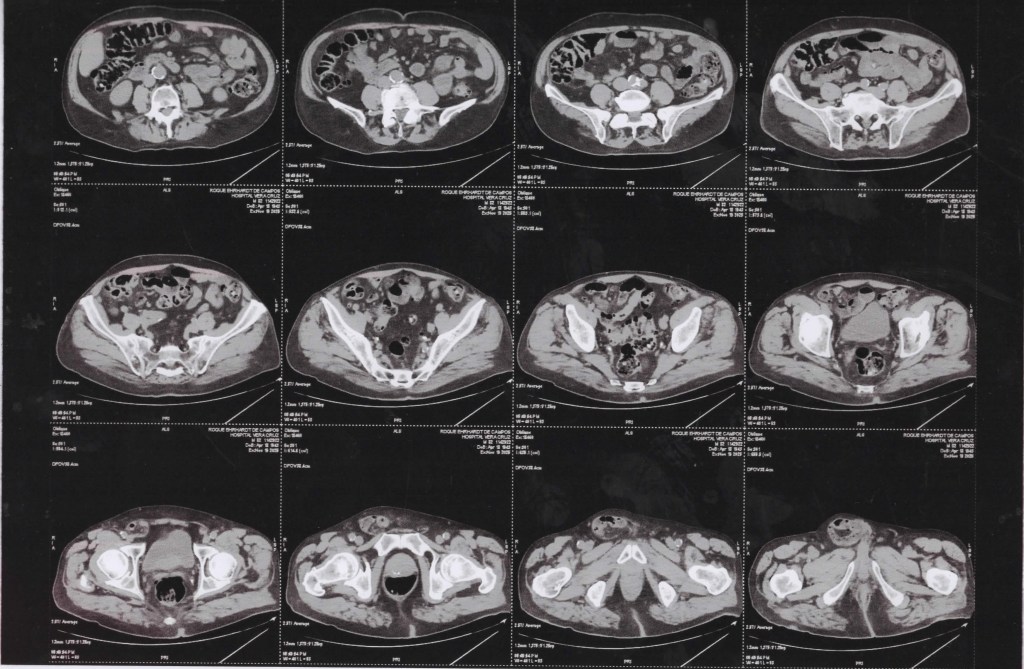

(TC) de Abdômen Superior com cortes axiais, em janela de tecidos moles, com contraste, focando principalmente no fígado.